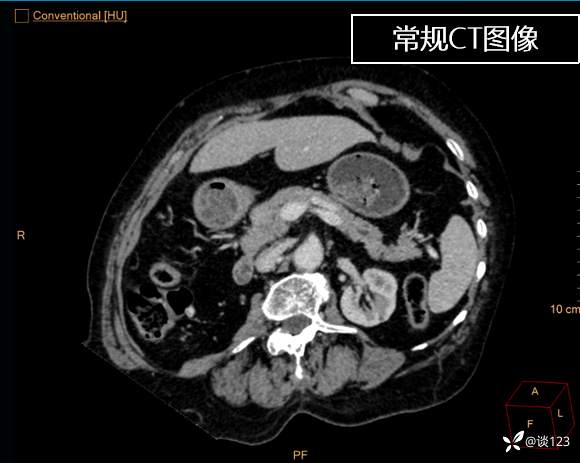

先做的CT:

重新针对CT进行多参数后处理

总结与讨论

这类病变不结合病史的情况,即使在CT静脉期有所异常也容易忽略;同时针对该类疾病使用胰腺增强方案应该更佳,好的诊断先决条件还是技术,技术不够CT新技术来凑。